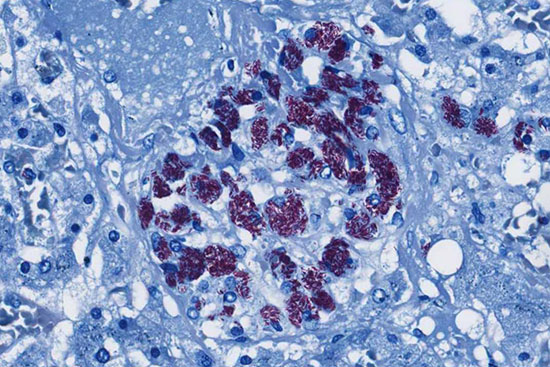

Some services performed in histogenotech :

- Surgery and biopsy

- Evaluation of brain Evans blue staining test in rats and mice